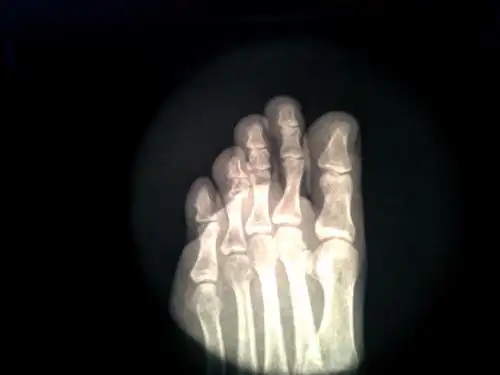

左足第四趾近节趾骨头骨折,长时间依然没有完全复位,该如何治疗,恢复